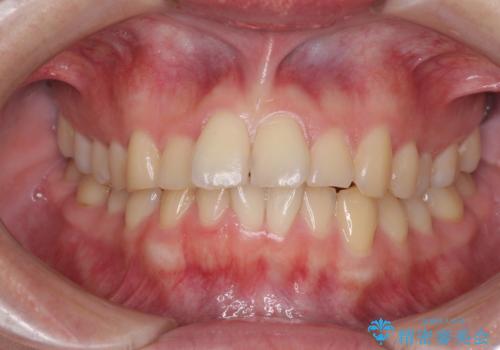

- 食いしばりが気になっていたとのことで来院された患者様です。

当初は睡眠時のマウスピースのみの製作をご希望でしたが、矯正治療の提案をしたところ、インビザラインにて矯正治療を行うこととなりました。

矯正治療中に食いしばりがより強くなることがあるため、半年に1回のペースでボツリヌストキシンによる咬合力緩和を並行して行うこととしました。

咬合力の緩和と食いしばりがちな咬み合わせが改善され、顎の負担が大幅に軽減されました。